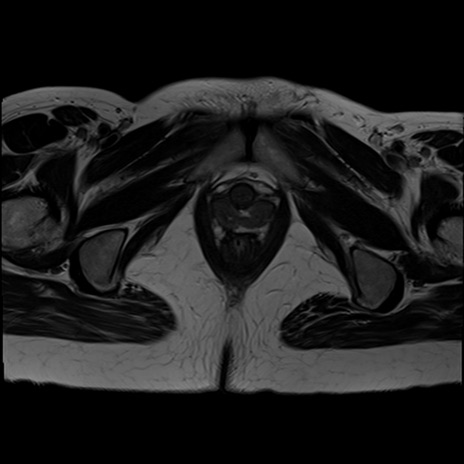

症例39 T2WI(横断像)

MRI(4日後)